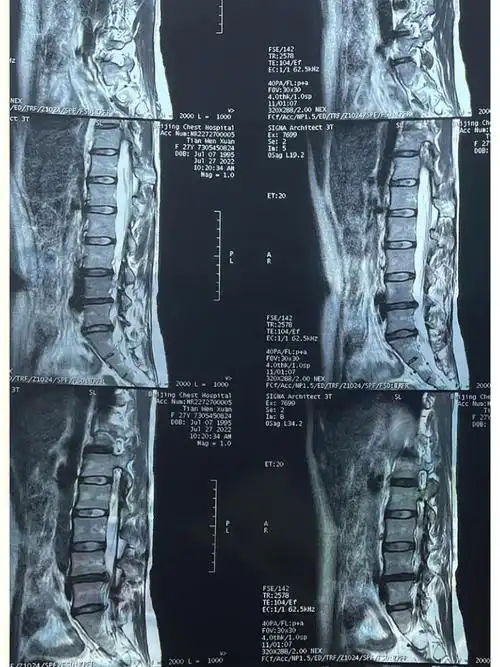

腰间盘突出

腰椎间盘突出

95我们可以看到,这个腰椎方方的,它是椎体,两个椎体之间就是椎间盘